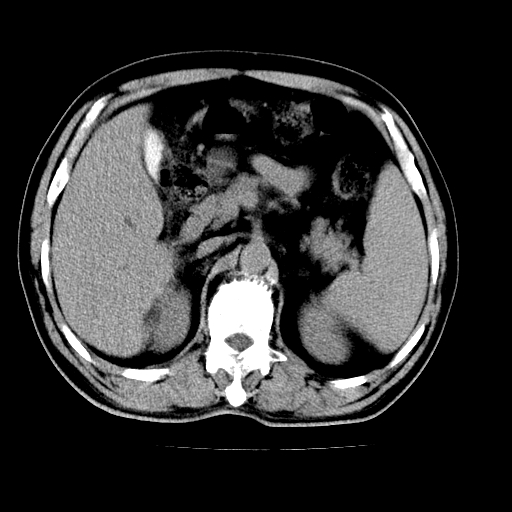

男,66岁,上腹部不适、黄染一周。彩超示:肝左叶占位,肝内胆管扩张,胆总管扩张,胆总管占位?

肝左叶不规则软组织肿块影,边缘不规整邻近肝实质受累分界不清;肝内胆管(左叶)明显扩张成“软藤状”,诊断:肝左叶胆管细胞癌。

肝左叶占位性病变,并胆管扩张,符合胆管细胞癌ct表现,门脉左支受累,左肾囊肿。窗宽太窄了,其他的看不清

左叶胆管细胞癌累及胆总管,门脉左支受侵,慢性胆囊炎胆结石,左肾小囊肿

肝左叶不规则软组织肿块影,边缘不规整邻近肝实质受累分界不清;肝内胆管(左叶)明显扩张成“软藤状”,诊断:肝左叶胆管细胞癌。胆囊钙乳症。